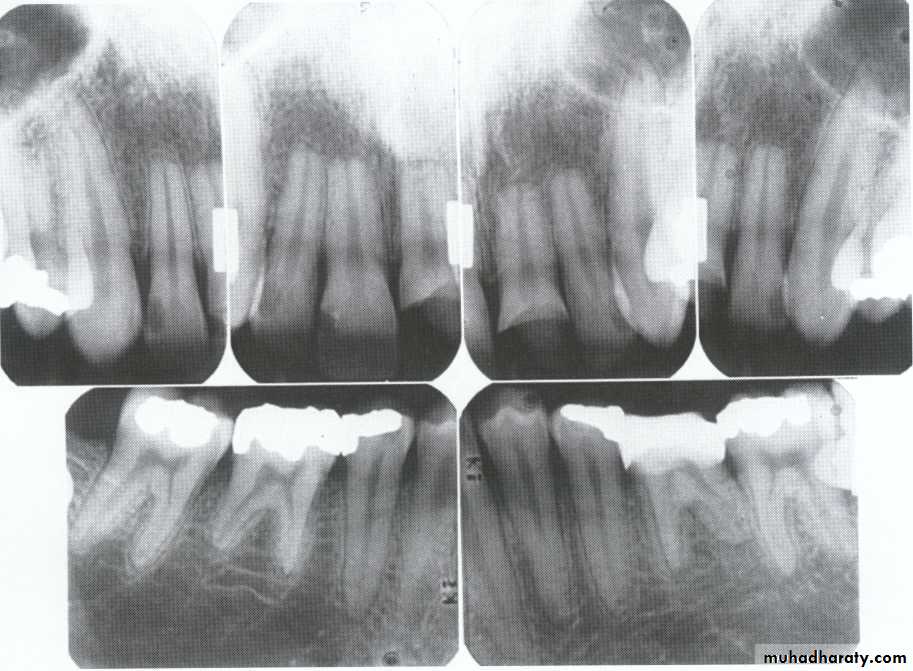

Radiographically:

Bulbous crownsCervical constriction

Thin roots

Early obliteration of roots canals & pulp chambers.

Roots are extremely short.

Pulps almost completely obliterated.

Periapical radiolucencies:

granulomas

cysts

chronic abscesses

Deciduous teeth:

roots are extremely short

pulps almost completely obliterated

Permanent teeth:

abnormally large pulp chambers in coronal portion of tooth.